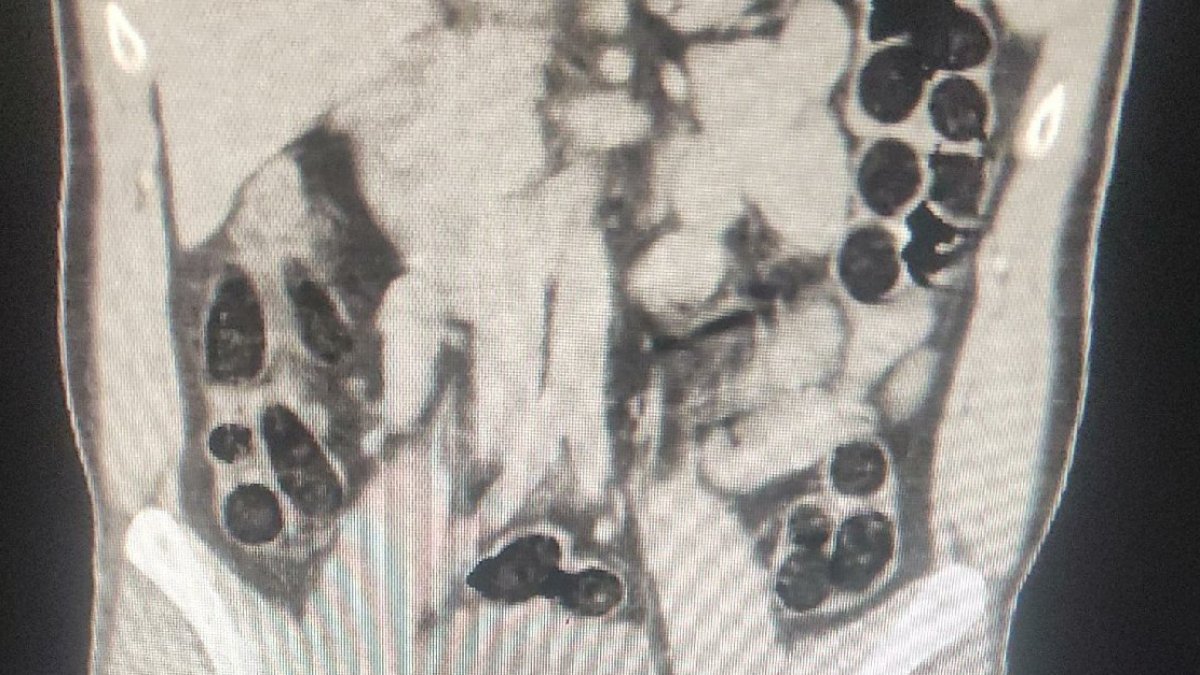

Yapılan yol kontrollerinde durdurulan otobüsteki İran uyruklu 2 kişi, şüpheli tavırları üzerine gözaltına alındı. Hastanede çekilen röntgenlerinde birinin midesinde uyuşturucu tespit edildi.

Şüphelinin, 76 paket halinde 714 gram eroini doğal yollarla çıkarılması sağlandı. Şüpheliler, emniyetteki işlemlerinin ardından sevk edildikleri adliyede çıkarıldıkları mahkemece tutuklanarak cezaevine gönderildi. (DHA)